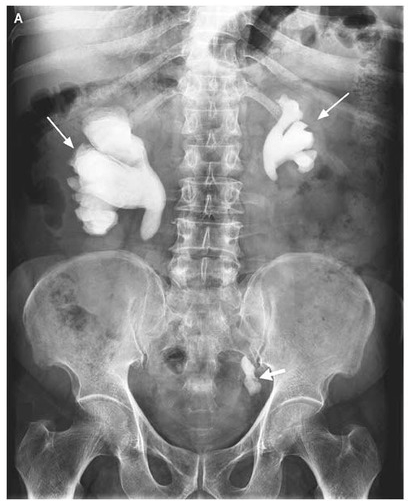

This is a staghorn calcui seen on xray.

What infection is this associated with?

proteus

-triphosphate crystals (seen with proteus)